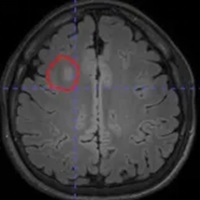

脑电图检查提示:右侧额叶异常放电。但常规头颅磁共振检查,始终未能发现明确的致痫病灶。面对这种情况,只能先通过药物控制病情。

借助医院先进的高清晰度、高对比度薄层扫描核磁共振,配合PET-CT检查,终于在右额叶发现了一个极其微小的致痫病灶。这个位置,与脑电图提示、以及临床发作特征完美吻合。更幸运的是,虽然病灶位置深,但范围很小。

640_副本

640 (1)_副本

这一发现,为精准治疗打开了大门。